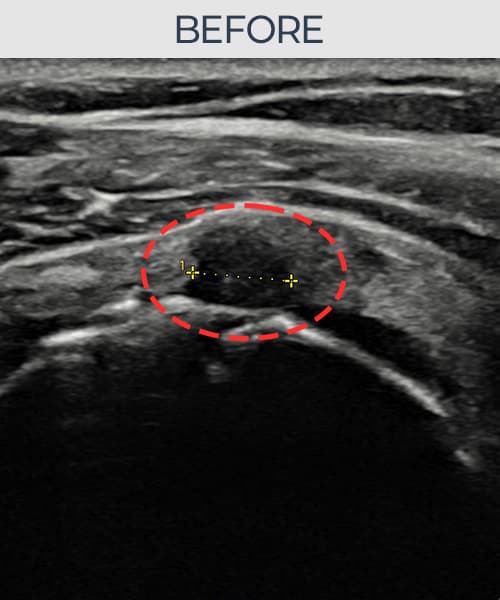

[経過期間: 23.07.31~23.09.27]

[縫縮術] 超音波検査にて左 棘上筋腱 부착부 광범위 部分断裂(13mm × 5mm (腱厚の約65%欠損))を確認。縫縮術施行後、腱の連続性が回復し、日常生活に復帰されました。